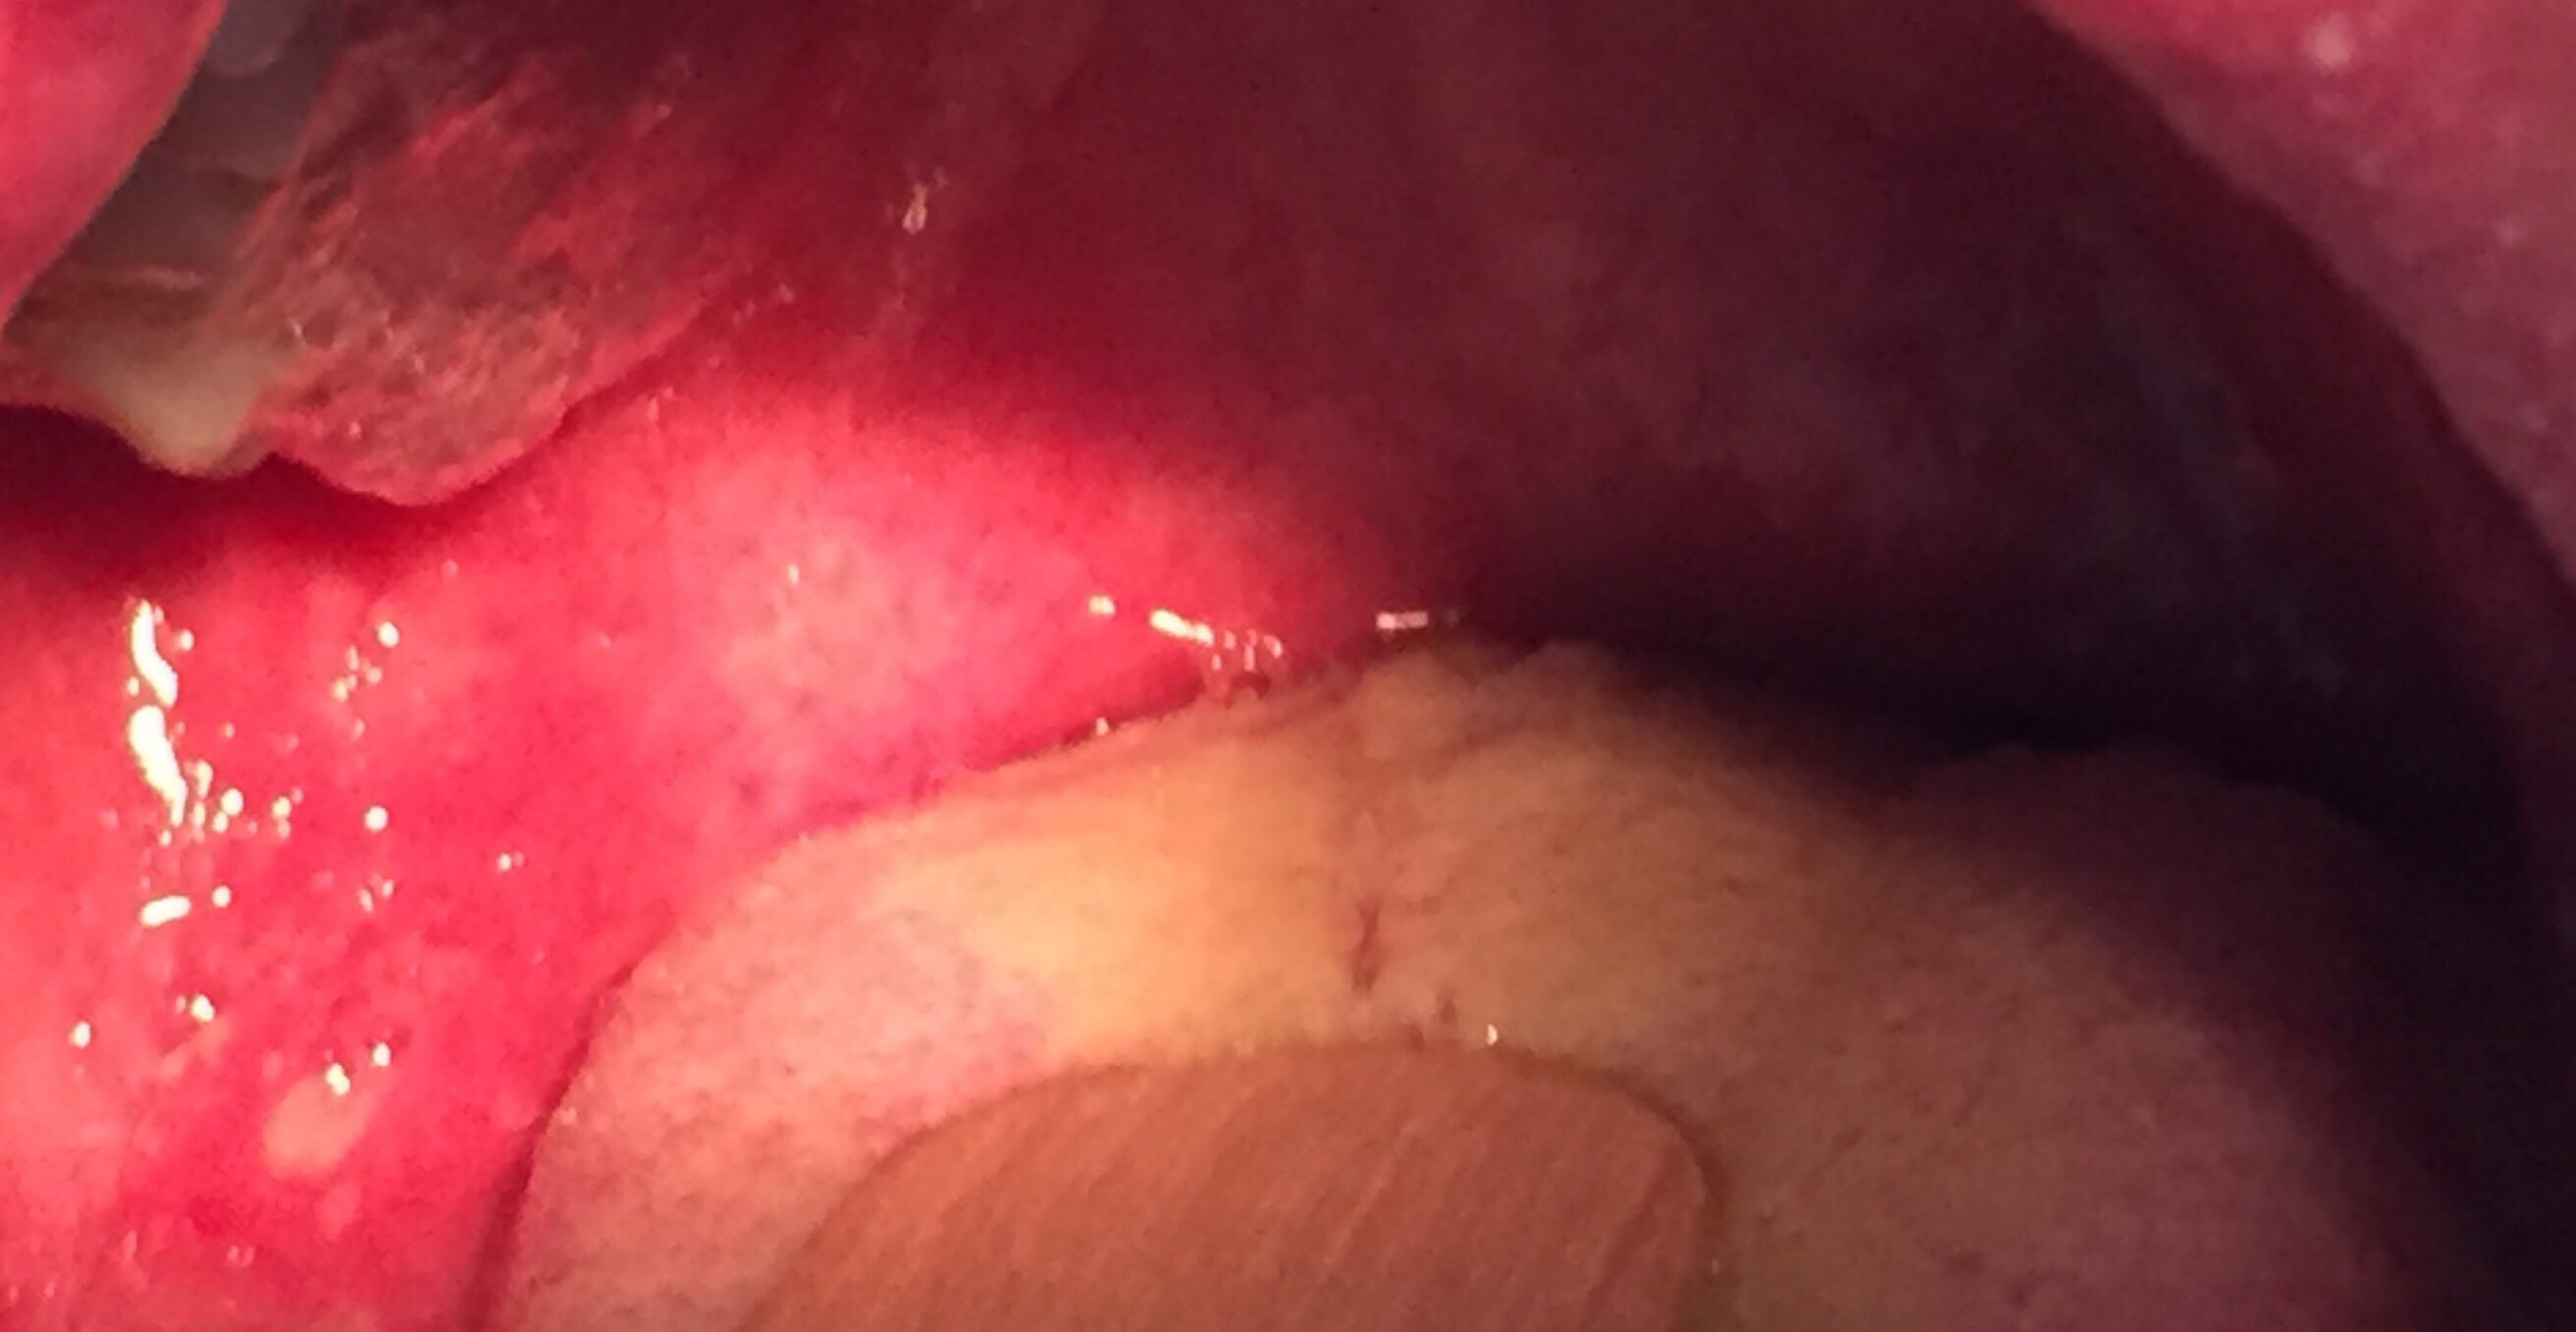

The diagnosis here is measles with a Koplik’s spot shown in the photo of the oral cavity. This is technically a clinical diagnosis, but due to the paucity of cases in Singapore, relatively few clinicians are likely to be confident in diagnosing this based on history and physical examination alone. Measles serology is unlikely to be positive within the first few days of illness, hence the way to confirm it would be to take a throat swab and send it for measles PCR test.